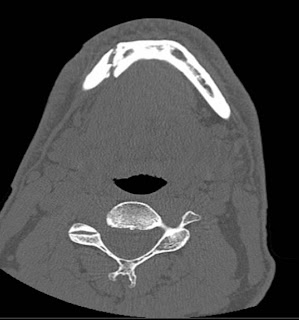

This right parasymphyseal mandibular fracture extends between a couple of teeth (no teeth lost--yet!):

I also have a comminuted (multi-part) fracture of the left subcondylar mandible: